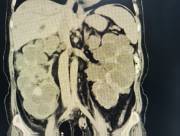

近日,西咸院区移植泌尿外科李智斌团队成功为一名复杂肾病患者同期实施“多囊肾切除+肾上腺肿瘤切除+肾移植术”。此次多术式联合手术,一次性解决了患者终末期肾病、巨大多囊肾及右侧肾上腺肿瘤三大难题,标志着三级片

在复杂器官移植领域取得了重要的突破。

该患者病情复杂,巨型多囊肾已对周围脏器造成严重压迫,同时肾上腺肿瘤导致原发性醛固酮增多症需长期口服药物治疗,而异体肾移植更是对手术精度和围术期管理有着极高要求。

手术过程中,李智斌带领团队沉着应对,精准解剖,在切除右侧巨型多囊肾和病变肾上腺之后,快速完成血管吻合,确保移植肾即刻恢复血流。整个手术历时近5小时,术后未出现并发症,现已转入普通病房康复。